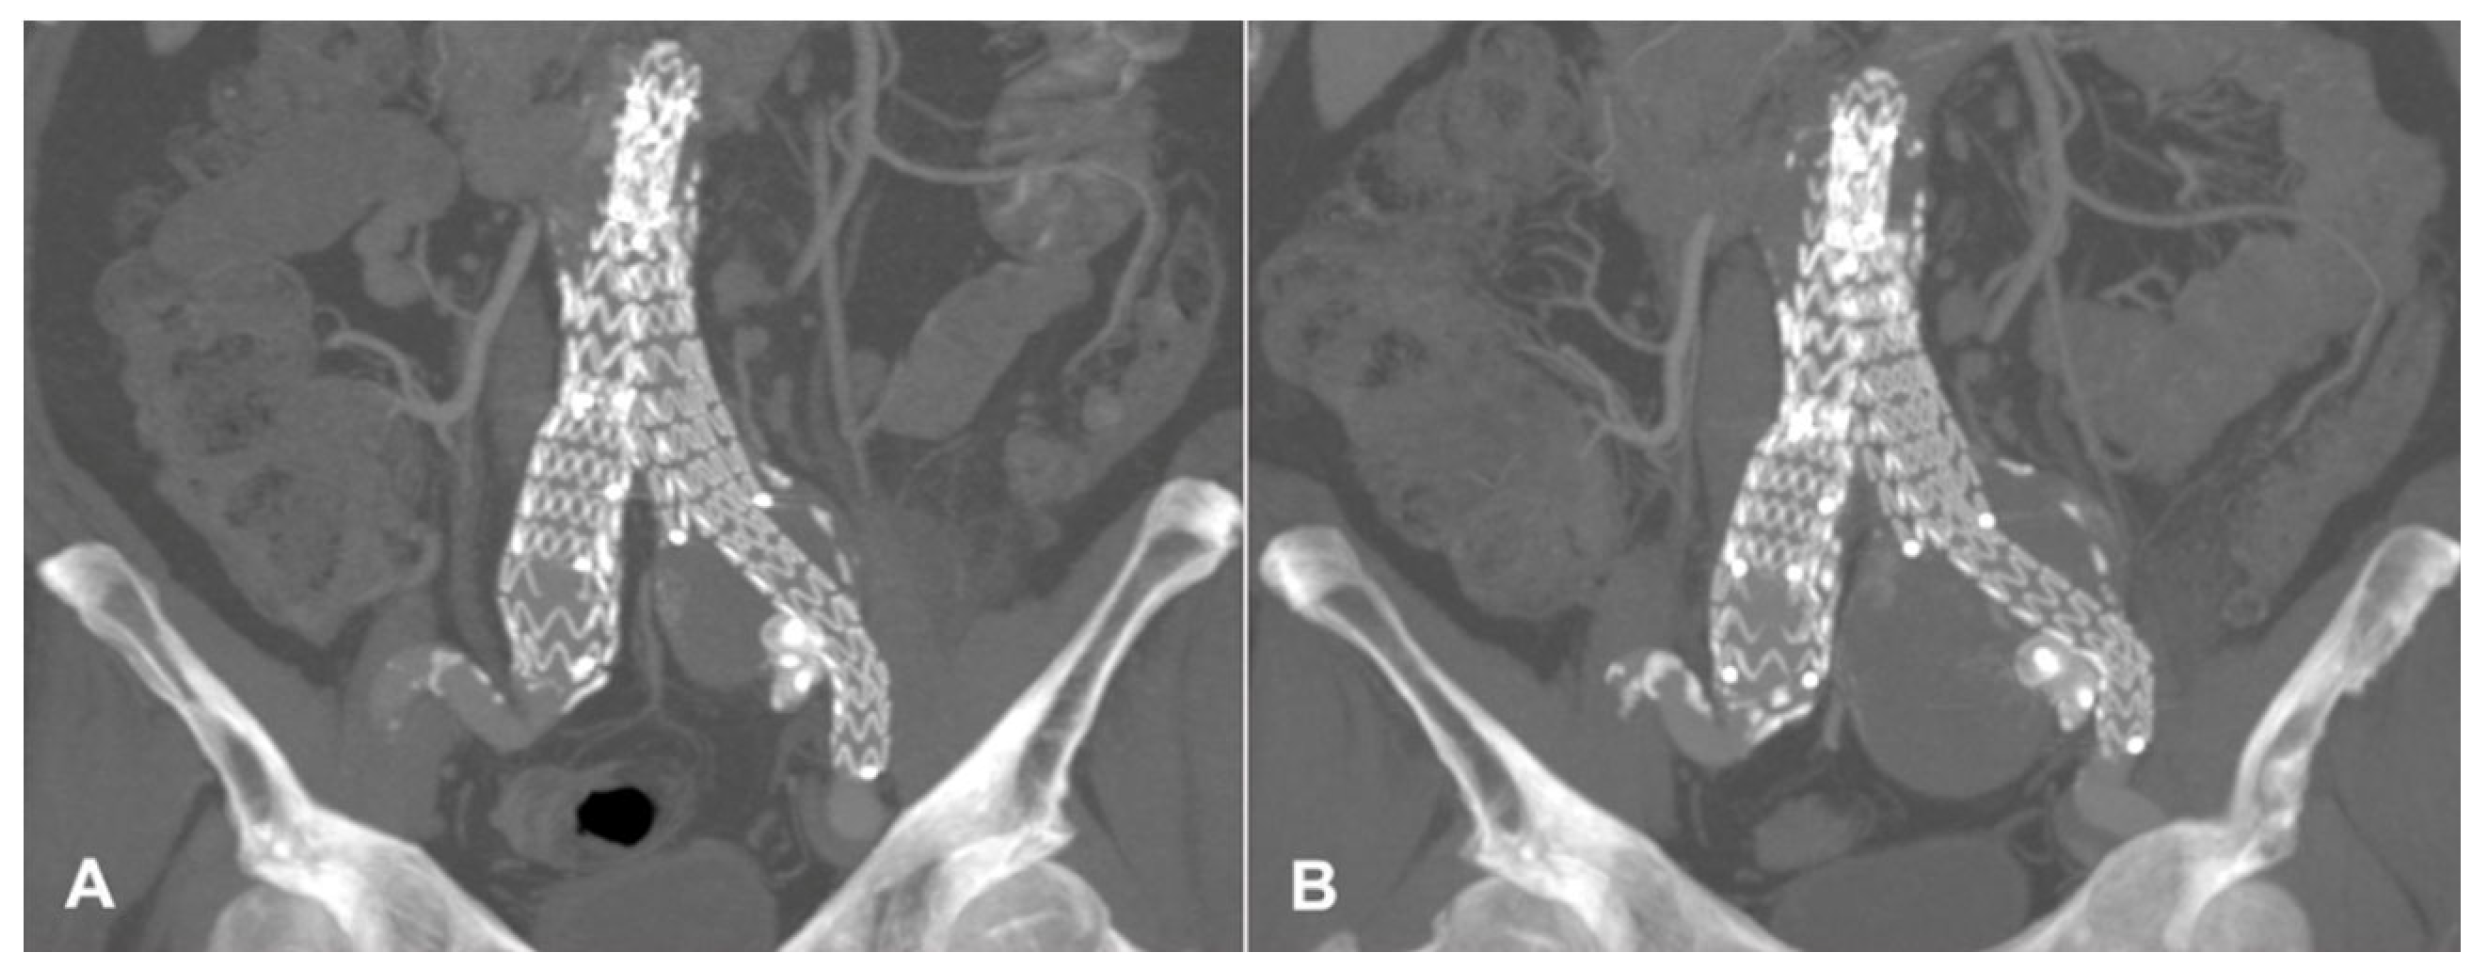

| Present case | Angiographic + DUS guided, 18G needle, sheathless |

Sac embolization with coils and liquid embolic agent | Manual compression | None | 12-months CT-scan, stable sac |